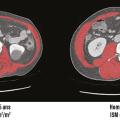

Les recommandations de la Haute Autorité de santé (HAS) publiées en 2019 ont reconnu la diminution de la force et/ou de la masse musculaire comme un critère phénotypique de la dénutrition.1 Parmi les outils recommandés chez l’adulte de moins de 70 ans figure l’évaluation de la surface musculaire en imagerie scanner. Néanmoins,…